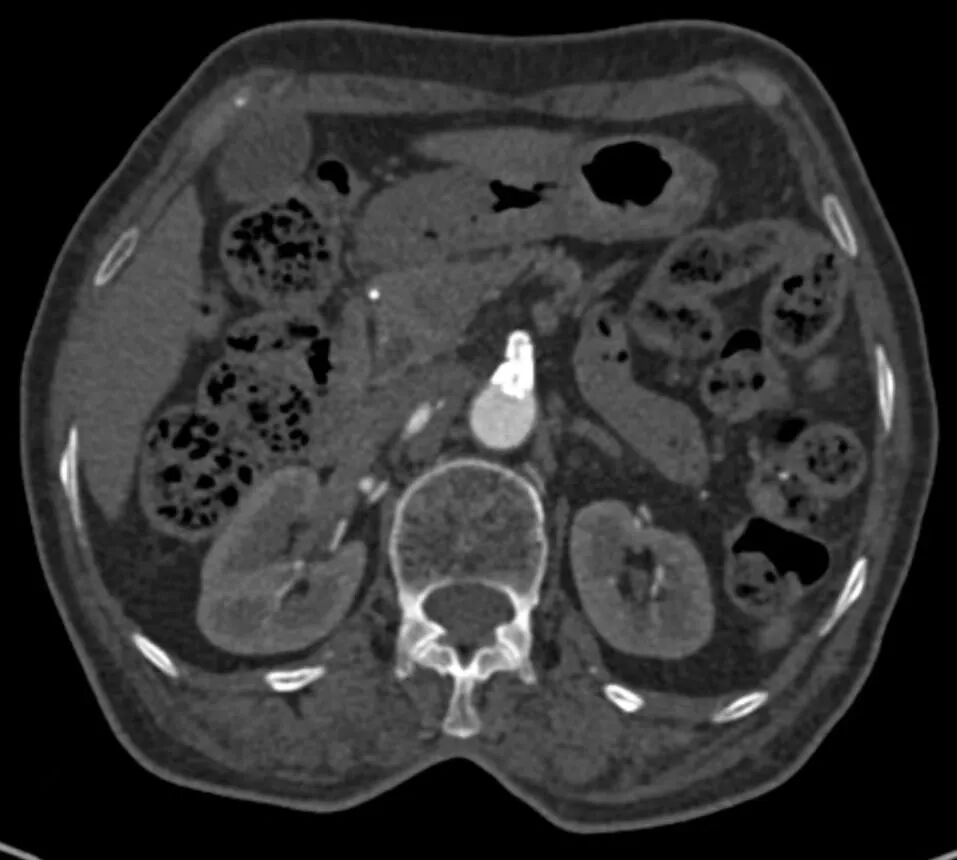

腹主动脉CTA:腹主动脉管壁见多发钙化、部分钙化斑块,管腔轻度狭窄。双肾动脉起始处见钙化斑块,管腔轻度狭窄,以远管腔显影可;腹腔干起始部可见部分钙化斑块,管腔狭窄程度约70%。脾动脉管壁见弥漫钙化斑块,管腔中-重度狭窄。肠系膜上动脉起始部见高密度支架,支架形态欠佳,局部腔内见多发钙化,管腔狭窄程度约70%。肠系膜下动脉见部分钙化斑块,管腔中度狭窄。

肠系膜上动脉开口